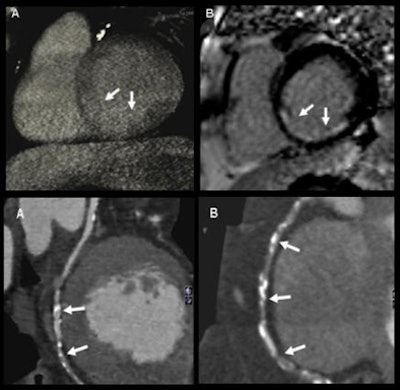

| Qualitative analysis: CT perfusion correctly classified 54 perfusion defects. Values for detecting myocardial perfusion defects at CT (versus SPECT) compared to MRI were as follows: 86% (84%) sensitivity, 98% (92%) specificity, 93% (88%) positive predictive value, and 94% (92%) negative predictive value. |

| Semiquantitative analysis: There were significant differences in upslope of signal intensity over time curve between normal and ischemic myocardium both with CT (above) and MRI (below). |

| Absolute quantification: Quantitative analysis showed significant differences in myocardial blood flow between normal and hypoperfused myocardium (p < 0.001); moderate correlation between absolute myocardial blood-flow quantification and upslope of signal intensity over time curves (r = 0.47, p < 0.01); and moderate correlation between myocardial blood flow and semiquantitative upslope for hypoperfused and normal myocardium (r = 0.41, p < 0.01 versus r = 0.43, p < 0.01). |